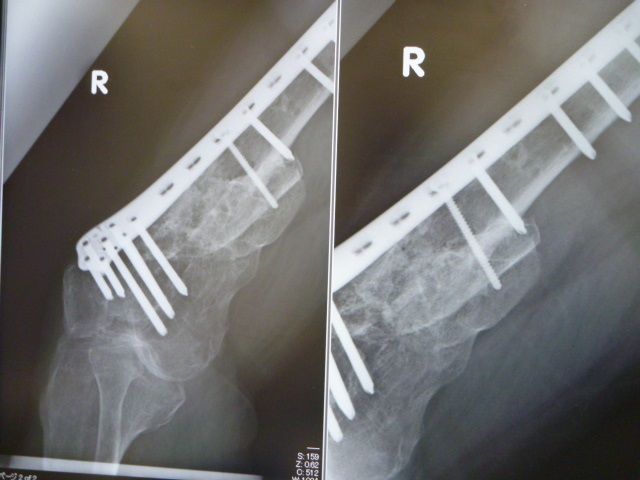

±¦¡¢È¾Ç¯Á°¤Î¥ì¥ó¥È¥²¥ó

º¸¡¢º£Æü¤Î¥ì¥ó¥È¥²¥ó

¹ü°Ü¿¢¤·¤Æ¤«¤é¡¢¤º¤Ã¤È¶õƶ¤À¤Ã¤¿Éôʬ¤¬

¤³¤³¤ËÍè¤ÆµÞ¤Ë¹ü¤¬³èÀ²½¤·¤Æ

¶õƶ¤¬Ëä¤Þ¤Ã¤Æ¤¤Æ¤¤¤Þ¤¹¡£

¶²¤é¤¯¤³¤ì¤Ï¡¢ËܳÊŪ¤Ë¥µ¡¼¥¥Ã¥È¤Ç

¥¹¥Ý¡¼¥ÄÁö¹Ô¤ò¤·¤¿°Ù¤À¤í¤¦¤È»×¤Ã¤Æ¤Þ¤¹¡£